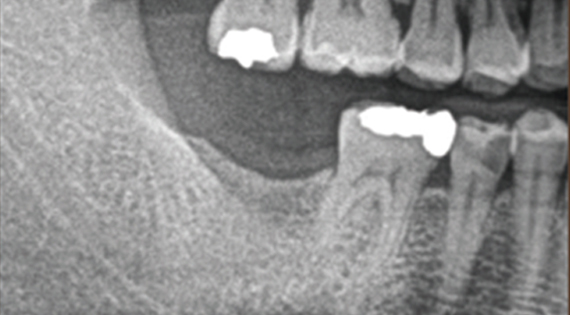

In the case of general cases, without opening the gingiva,

Magic GPS is used to easily and accurately Implants can be placed.